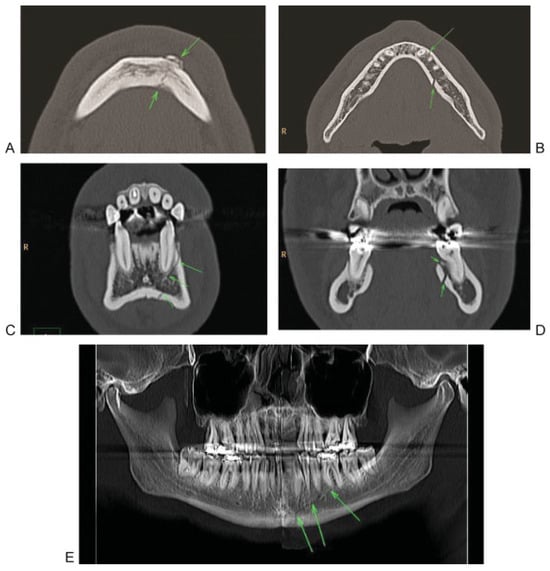

Systematic evaluation of the midface in CT begins with the evaluation of axial slices from caudal to cranial (Figure 2A–C) to detect direct fracture signs, especially in the lower central midface (including alveolar process, caudal part of nasomaxillary buttress), intermediate central midface (including anterior sinus walls), upper central midface (including frontal process maxilla, lacrimal bone and nasal bones). In the axial plane the zygoma and zygomatic arch are evaluated with all its relationships to the central midface. Subsequently, the orbital rims as well as lateral and medial orbital walls are assessed. In a second step coronal 2D reconstructions (Figure 2E,F) are checked for the integrity of the nasomaxillary buttress in the lower and intermediate central midface regions, the frontal process of the maxilla and the nasal bones in the anterior coronal reconstructions (Figure 3). The integrity of the palate and the pterygoid plates should also be checked in the coronal plane, which ideally should be perpendicular to the palate. Furthermore the medial orbital walls, the orbital floors and orbital roofs are well detected in the coronal plane. The orbital apex regions are search for integrity, especially of the optic nerve canal. Additional 2D reconstructions for the orbital floor through the axis of the intraorbital nerve may be useful in detecting displaced fractures with muscle entrapment or retrobulbar hematoma. 3D CT reconstructions may not add significant information for level 2 classification (Figure 2G–I).

Figure 2. Systematic analysis of a midfacial fracture. (A) Axial slice: evaluation of the lower central midface with fracture of the zygomatic alveolar crest, anterior and dorsolateral maxillary sinus wall (arrows). (B) Axial slice: Involvement of the zygomatic arch with multiple fractures (arrows). (C) Axial Slice: Fracture of the anterior part of the lateral wall (arrows). (D) Two-dimensional coronal reconstruction at level frontogygomatic buttress (no fracture). (E, F) Two- dimensional coronal reconstruction with the fractures at the zygoma and anterior part of the lateral orbital wall and fronto-zygomatic suture (arrows). (G–I) Three-dimensional reconstruction showing the involvement of the right zygoma, intermediate and lower central midface and orbit.